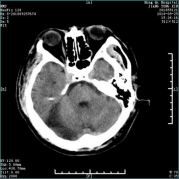

急性脑梗死的教学案例 专业知识 脑梗死(cerebral infarction,CI)又称缺血性脑卒中,是指各种原因所致脑部血液供应障碍,导致脑组织缺血、缺氧性坏死,而出现相应神经功能缺损的一类临床综合征。 案例 孙某,男,主因“发现言语不清、左侧肢体活动不灵1小时10分”入院。患者于14:30左右起床时发现言语含糊不清,吐字费力,口角歪斜,左侧肢体活动不灵,表现为左上肢无法抬起,左下肢无法行走,伴头晕,视物不适,无头痛,无恶心、呕吐,无视物旋转,无一过性黑矇,无意识障碍,无胸闷、气短。为求进一步诊治急来我院就诊。患者今日中午13:30睡午觉时无言语不清,无左侧肢体活动不灵。既往高血压病史10年余,平素血压最高达 210/120mmHg,未规律系统用药;否认心脏病、糖尿病病史。 查体:体温:36.5℃,血压:163/100mmHg,呼吸:20次/分,双肺呼吸音清,心率89次/分,腹软,双下肢无浮肿。神经系统查体:意识清,构音障碍,左侧瞳孔大约5.0mm,右侧瞳孔大约3.0mm,对光反射灵敏,水平眼震,左侧同向性偏盲,右侧头面部麻木,右侧周围性面瘫,伸舌居中,左上肢近端肌力2级,远端肌力2级;左下肢近端肌力3-级,远端肌力3-级,右侧肌力5级,四肢肌张力正常,腱反射(++),左侧Babinski(+),颈软,克氏征(-),NIHSS评分:9分。急查头部CT示:右侧枕叶低密度影。